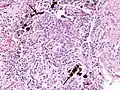

Asbestosis is the scarring of lung tissue (beginning around terminal bronchioles and alveolar ducts and extending into the alveolar walls) resulting from the inhalation of asbestos fibers. There are two types of fibers: amphibole (thin and straight) and serpentine (curly). All forms of asbestos fibers are responsible for human disease as they are able to penetrate deeply into the lungs. When such fibers reach the alveoli (air sacs) in the lung, where oxygen is transferred into the blood, the foreign bodies (asbestos fibers) cause the activation of the lungs' local immune system and provoke an inflammatory reaction dominated by lung macrophages that respond to chemotactic factors activated by the fibers.[19] This inflammatory reaction can be described as chronic rather than acute, with a slow ongoing progression of the immune system attempting to eliminate the foreign fibers. Macrophages phagocytose (ingest) the fibers and stimulate fibroblasts to deposit connective tissue. Due to the asbestos fibers' natural resistance to digestion, some macrophages are killed and others release inflammatory chemical signals, attracting further lung macrophages and fibrolastic cells that synthesize fibrous scar tissue, which eventually becomes diffuse and can progress in heavily exposed individuals. This tissue can be seen microscopically soon after exposure in animal models. Some asbestos fibers become layered by an iron-containing proteinaceous material (ferruginous body) in cases of heavy exposure where about 10% of the fibers become coated. Most inhaled asbestos fibers remain uncoated. About 20% of the inhaled fibers are transported by cytoskeletal components of the alveolar epithelium to the interstitial compartment of the lung where they interact with macrophages and mesenchymal cells. The cytokines, transforming growth factor beta and tumor necrosis factor alpha, appear to play major roles in the development of scarring inasmuch as the process can be blocked in animal models by preventing the expression of the growth factors.[20][21] The result is fibrosis in the interstitial space, thus asbestosis. This fibrotic scarring causes alveolar walls to thicken, which reduces elasticity and gas diffusion, reducing oxygen transfer to the blood as well as the removal of carbon dioxide. This can result in shortness of breath, a common symptom exhibited by individuals with asbestosis.[22]

Asbestosis resembles many other diffuse interstitial lung diseases, including other pneumoconiosis. The differential diagnosis includes idiopathic pulmonary fibrosis (IPF), hypersensitivity pneumonitis, sarcoidosis, and others. The presence of pleural plaques may provide supportive evidence of causation by asbestos. Although lung biopsy is usually not necessary, the presence of asbestos bodies in association with pulmonary fibrosis establishes the diagnosis.[24] Conversely, interstitial pulmonary fibrosis in the absence of asbestos bodies is most likely not asbestosis.[11] Asbestos bodies in the absence of fibrosis indicate exposure, not disease.

The arrow points to an uncoated segment of asbestos fiber in this ferruginous body.

The black arrows point to ferrugionous bodies that are located at the periphery of a focus of non-small cell lung carcinoma, NOS.